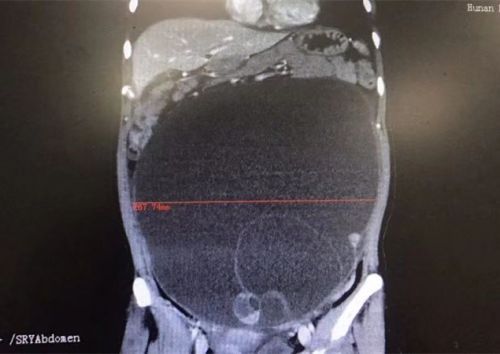

全腹ct显示肿块巨大。

入院完善腹部CT结果显示,比篮球大的肿瘤不仅占据盆腔,还长到腹腔内,考虑左侧卵巢来源黏液性囊腺癌的可能性大。完善术前准备后,3月1日,闵小佳带领手术团队在全麻下为陈女士施行卵巢癌全面分期手术,将被肿瘤侵犯的子宫、双侧附件、大网膜、阑尾切除,并进行盆腔淋巴结清扫和盆腔粘连松解。手术过程顺利,术中发现左侧卵巢囊样增大至约30×25×28cm3大小,切下来的肿瘤装了整整一脸盆,足有10余斤。